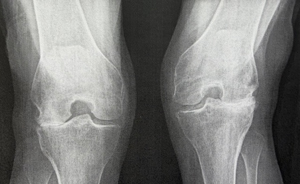

Lynnie Before XR

I can't believe the picture of my legs before and after…I was so relieved to get back to Calgary and not have to think about planes and cars and hotels and reservations. You were the most relaxing part of this whole adventure. Honestly, I felt soooooo cared for and in such capable hands and I was sooo out of it….I didn't even dream. It just all happened. And you and Angie and your dream team, I’m soooo grateful. United Airlines lost my walker..…but we eventually made it safely here to an empty quiet comfortable home in Calgary… and slept… and thus my legs and body have stopped spasming, but I will go get muscle relaxers if they start again. Right now, all I have to do is ice and rest and marvel at my legs as I walk to the bathroom. My left leg as you know was the weirdest one and it is amazing. The right one every once in while feels like it might give way, but I think it's just cause I get too enthusiastic… (on a very very slow scale)…..and my feet are learning too… and they feel better, amazingly, which is so reassuring. I didn't want them to wreck your beautiful work. Gosh this so magic… and yet this is science and talent and thank you for going to school and learning all of this.